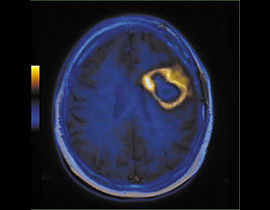

Mit der MRT können sowohl anatomische als auch physiologische Merkmale von Organen und Pathologien erkannt werden. Diese Vielseitigkeit macht die Bildgebungsmethode zu einem unverzichtbaren Diagnosewerkzeug. AW-Programme mit ihren vereinfachten Abläufen und intuitiver Benutzeroberfläche ermöglichen dem Anwender eine rasche und präzise Quantifizierung und qualitative Auswertung von MR-Untersuchungsergebnissen.

Erweiterte Visualisierung für PET